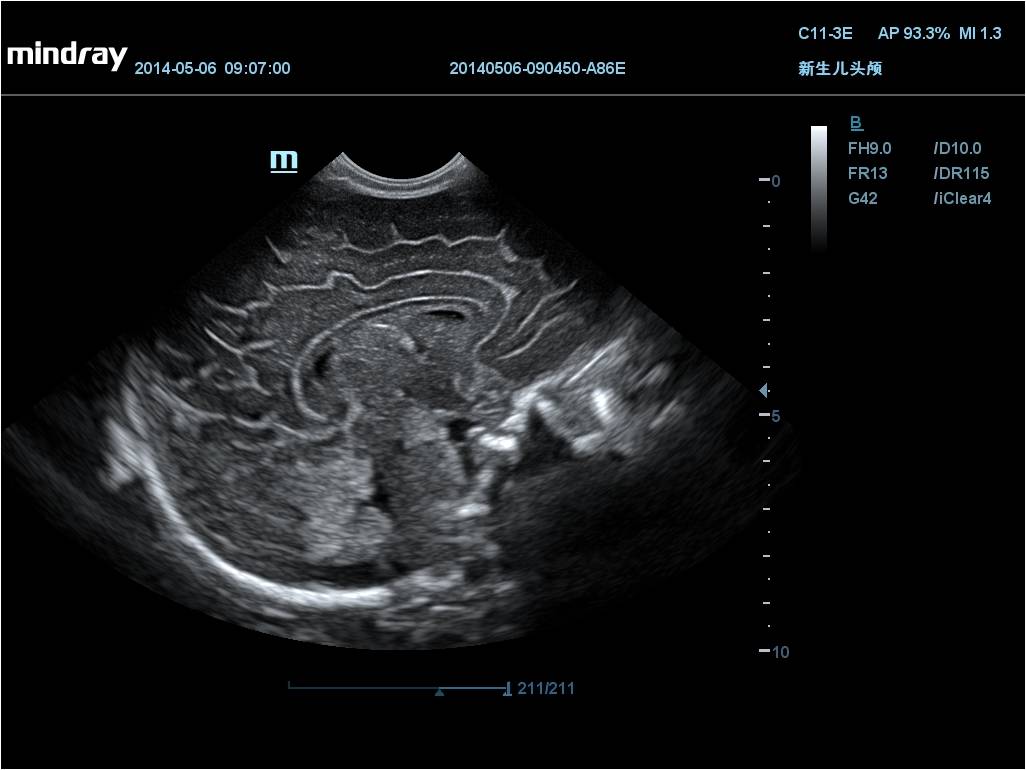

iScape Функция панорамной визуализации, возможность отображения скорости передвижения используемого датчика в момент проведения процедуры и сканирования в двух направлениях.